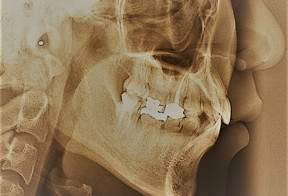

Home > Press > A Tougher Tooth: A new dental restoration composite developed by UCSB scientists proves more durable than the conventional material

A Tougher Tooth: A new dental restoration composite developed by UCSB scientists proves more durable than the conventional material